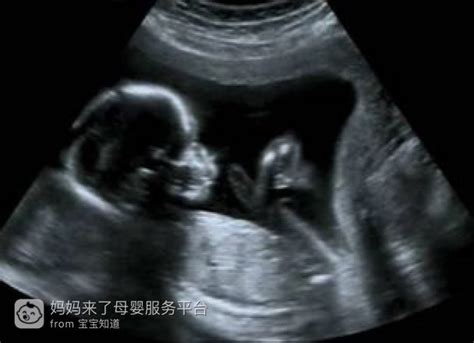

我的产检B超单子,麻烦懂的人帮我看看,附超声图

报告单的整个内容是表述胎儿的发育状况和胎盘在宫内的位置。绝对没有胎儿性别的描述,鉴别性别是违法的,不会写在报告单上。胎儿的性别,在做B超时可以直接看到。你如果真想知道是男孩女孩,你可以和超声大夫沟通沟通,一般情况下能问出来。 另外,图像显示的是胎儿心脏部位的切面图,并非嘴巴,你说的“绕着脖子连到嘴巴上的那个”是胎儿的上肢或下肢。看着图片不要胡猜,那样会自己把自己吓坏的。 保存着这幅图片吧,以后把它和宝宝的成长记录相片等放到一起,很有意义的!